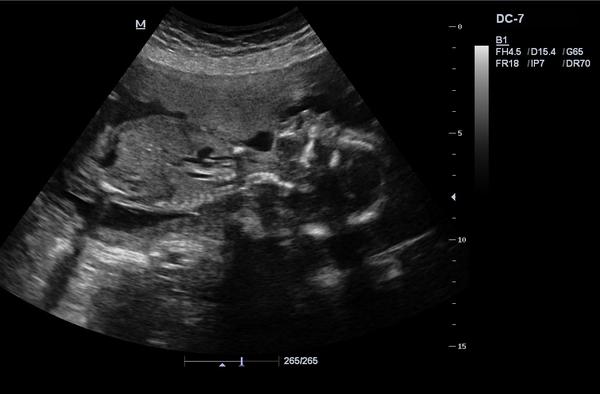

dá se prosím rozpoznat pohlaví?

Pokud ano, tak co myslíte?

bohužel nedá. ☹